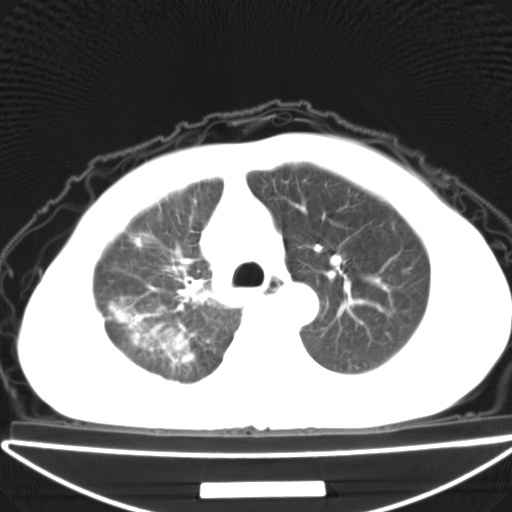

以下是引用jsgdoctor在2008-11-6 22:12:00的发言:[br]右主支气管壁明显增厚,管腔狭窄.考虑为右侧中央型肺癌伴阻塞性炎症\\肺脓肿.

以下是引用zjzjr在2008-11-6 20:25:00的发言:[br]中心型肺ca,合并阻塞性肺炎

以下是引用zsl6918在2008-11-6 19:43:00的发言:[br]右侧中心性肺癌(鳞癌)